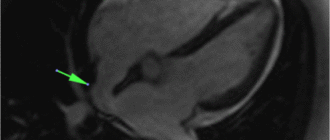

Кт и мрт диагностика дефекта межпредсердной перегородки 1/3 всех ВПС дефект межпредсердной перегородки сердца